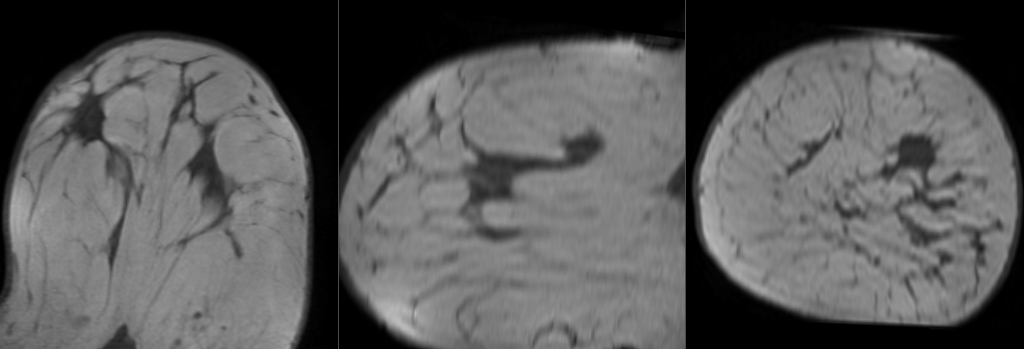

File:RegLib C06 Affine.gif

Original file (1,024 × 349 pixels, file size: 460 KB, MIME type: image/gif)